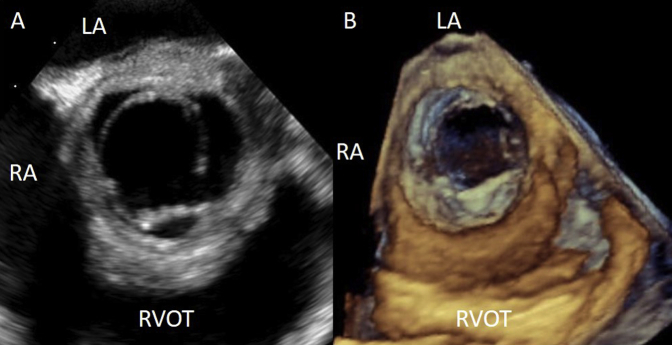

The presence of moderate to severe AR, a thickened aortic root, and a pericardial effusion increased suspicions for an acute aortic syndrome, such as aortic dissection or intramural hematoma. As per institutional practice, emergent transesophageal echocardiography was then performed and confirmed the findings on transthoracic echocardiography (Figures 2A and 2B, Video 5, Video 6, Video 7, Video 8). There was malcoaptation of the left and right coronary cusps of the AV resulting in a moderate to severe AR. The walls of the aortic root and proximal ascending aorta were thickened, and the sinotubular junction was effaced. There was no evidence of aortic dissection.

Figure 2.

(A) Transesophageal echocardiographic (TEE) image from the midesophageal window at 50° showing a tricuspid AV with a thickened aortic root. (B) TEE three-dimensional rendered image of the AV during systole as seen from the aorta. LA, Left atrium; RA, right atrium; RVOT, right ventricular outflow tract.

Two-dimensional transesophageal echocardiogram of a midesophageal short axis view of the aortic valve demonstrating the thickened walls of the aortic root.

Three-dimensional transesophageal echocardiographic reconstruction of the aortic valve as viewed from the aorta demonstrating the thickened walls of the aortic root.